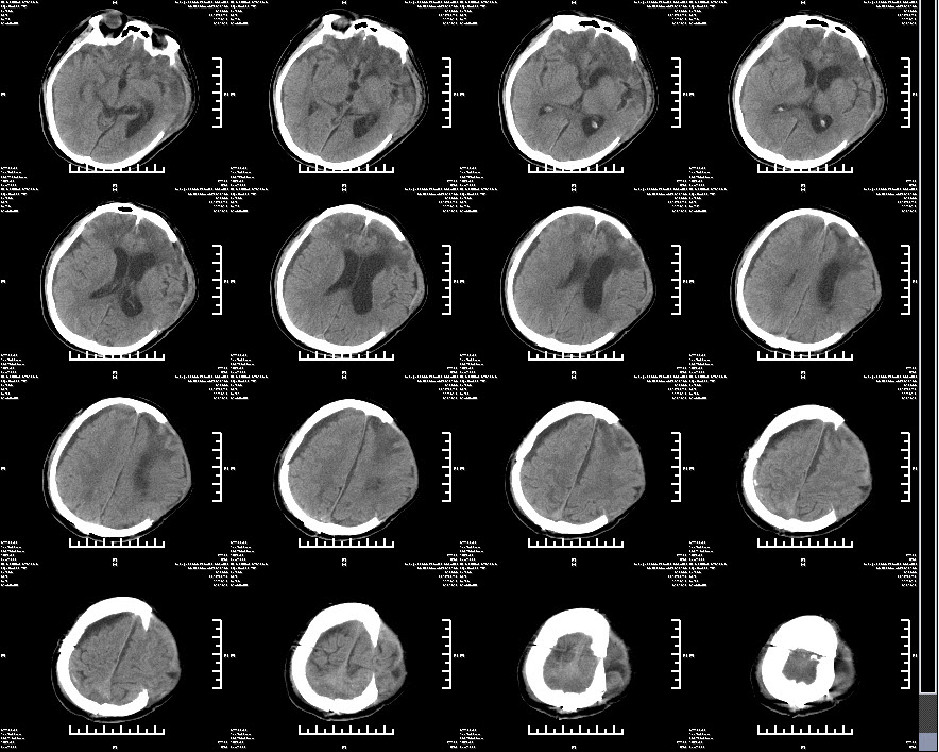

2019年4月18日头颅CT:行颅骨修补+VP-分流术

2019年4月30日术后头颅CT

患者半年后随访